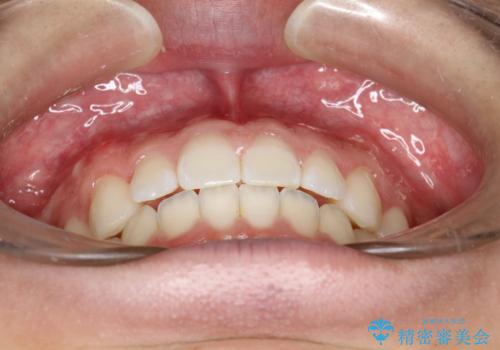

前歯の隙間がきになる インビザラインですきっ歯の治療

- 上の前歯の隙間を主訴に来院されました。

正中に隙間があり、かみ合わせが深い過蓋咬合という状態でした。

インビザラインにて矯正治療を行いました。

しっかり使っていただけたので、スムーズに治療を終了することができました。